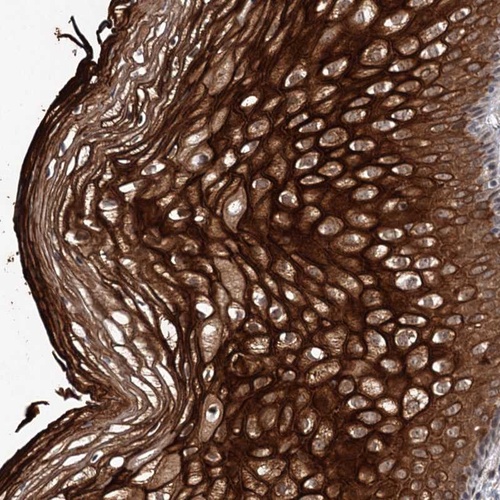

Immunohistochemical staining of human vagina shows strong cytoplasmic and membranous positivity in squamous epithelial cells.